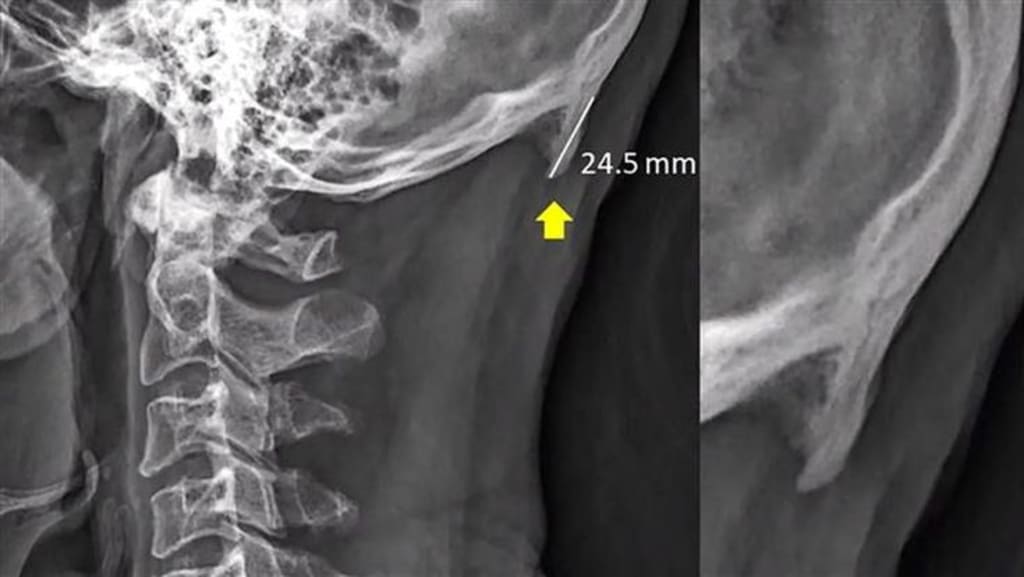

In reality, the EOP is a bony growth nestled at the back of the skull, intricately connected to the nuchal ligament. The nuchal ligament, a wise connector, plays a crucial role in linking neck muscles to the skull, while the EOP acts as an anchor, bestowing stability upon this connection. The plot thickens when we consider Shahar and Sayers' startling revelation—during their extensive study, they unearthed something astonishing. In young people, the EOP seemed to be more prevalent, prompting them to hypothesize that the forward-leaning posture adopted during prolonged smartphone and tablet use is a key factor.

As we crane our necks forward to gaze at our screens, we unwittingly apply extra pressure to the region where neck muscles connect to the skull. To compensate, the EOP gradually elongates, growing by several millimeters. This fascinating phenomenon has even earned itself a nickname: "text neck."